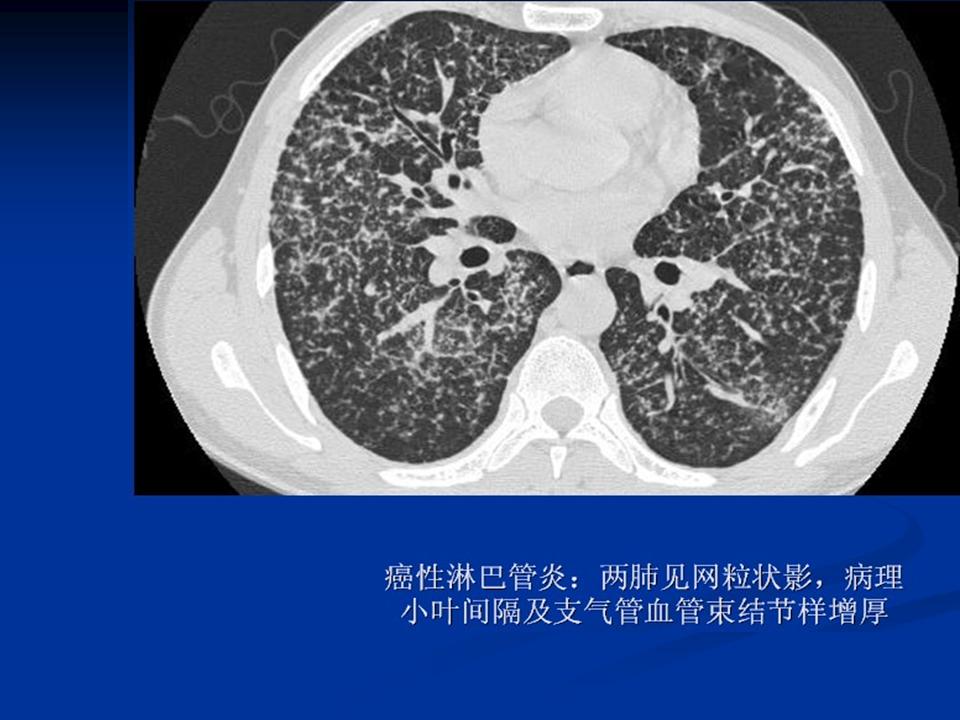

肺转移瘤与韦格肉芽肿影像鉴别